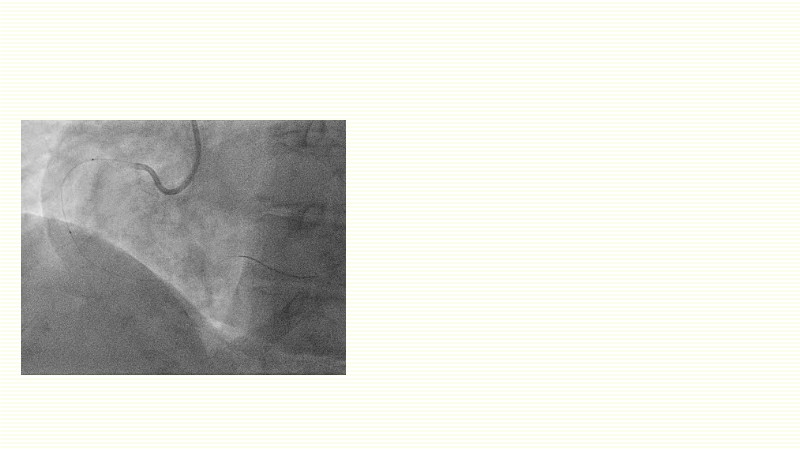

This EuroPCR 2025 session challenges the conventional approach to bifurcation PCI and dissection management. Learn why drug-coated balloons (DCB) may offer better long-term outcomes in cases where stents fall short, how DCBs can simplify bifurcation strategies, and why it’s time to rethink which dissections really need stenting. Through data, case examples, and clear decision-making insights, you'll gain the confidence to broaden your DCB practice where it truly matters.

- To analyse clinical data and use case of drug-coated balloons in bifurcation PCI